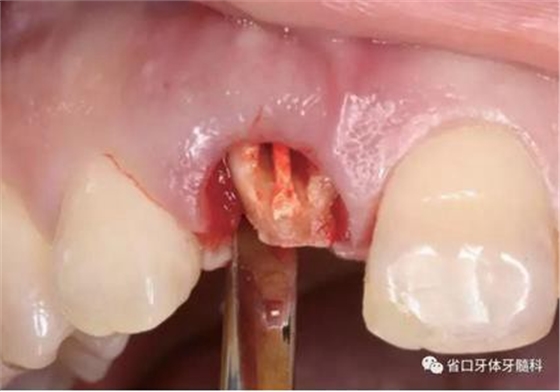

圖5 微創(chuàng)拔牙

圖6 微創(chuàng)拔牙

(1)微創(chuàng)拔牙及即刻種植:術(shù)前拍攝口內(nèi)照及實(shí)施牙周基礎(chǔ)治療。常 規(guī)消毒鋪巾阿替卡因局麻下微創(chuàng)拔除上頜右側(cè)中切牙,搔刮拔牙窩及根尖肉 芽組織。探測牙槽骨唇側(cè)骨壁及鄰面牙槽嵴完整,牙齦無撕裂。不翻瓣下于上頜右側(cè)中切牙缺隙近遠(yuǎn)中中點(diǎn)的腭側(cè)牙槽骨及根方定位,按照逐級預(yù)備的原則,緊貼牙槽窩腭側(cè)骨壁制備種植窩洞,植入Zimer®3.7mm×13mm TSV種植體1顆,植入扭矩>35N·cm,以O(shè)sstell測量種植體的ISQ值為68。 種植體平臺位于唇側(cè)齦緣中點(diǎn)下3mm,與唇側(cè)骨壁內(nèi)側(cè)面形成的跳躍間 隙約2mm,置入Bio-Oss®細(xì)顆粒骨粉0.25g,上愈合基臺關(guān)閉創(chuàng)口。術(shù)后 CBCT檢查顯示:種植體利用牙槽窩根方骨質(zhì)固位,緊貼牙槽窩腭側(cè)骨壁, 其唇側(cè)面與牙槽窩唇側(cè)骨壁的內(nèi)側(cè)面所形成的跳躍間隙(約2mm)可見顆 粒狀顯影物充填。牙槽窩的唇側(cè)骨壁及唇側(cè)倒凹無缺損穿孔。